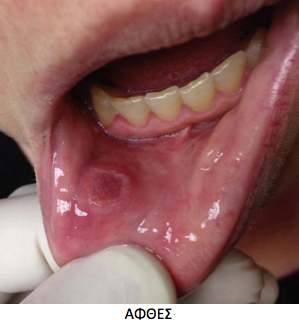

Τι είναι η βλεννογονίτιδα

Βλεννογονίτιδα αναφέρεται ως την φλεγμονώδη διεργασία των βλεννογόνων της στοματικής κοιλότητας και της γαστρεντερικής οδού. Η στοματίτιδα παραπέμπει σε φλεγμονώδεις καταστάσεις του στόματος συμπεριλαμβάνοντας όχι μόνο του βλεννογόνου, αλλά και της οδοντοφυΐας, του ακροριζίου και του περιοδοντίου. Χρησιμοποιείται επίσης ο όρος βλεννογονίτιδα της πεπτικής οδού, για βλεννογονίτιδα στη στοματική κοιλότητα και της γαστρεντερικής οδού ως μία ένοια.

Στην ξηροστομία μειώνεται ή ροή του σιέλου και μπορεί ή όχι να συνοδεύεται από βλεννογονίτιδα. Οι ποικίλοι βαθμοί σοβαρότητας της βλεννογονίτιδας σε ασθενείς που λαμβάνουν κυτταροτοξική θεραπεία κυμαίνονται από ήπιες αλλαγές αίσθησης, έως συρρέουσες, ελκώδης, αιμορραγικές βλάβες. Οι βλάβες αυτές μπορεί να είναι παρούσες σε όλη τη στοματική κοιλότητα και του γαστρεντερικού σωλήνα.

Τα συμπτώματα των ασθενών που σχετίζονται στην από του στόματος βλεννογονίτιδα περιλαμβάνουν αλλαγές στην αίσθηση, δυσκολία ομιλίας και κατάποσης, παρουσία πληγών και μερικές φορές ξηρότητας. Ακόμη εμφανίζονται συμπτώματα, όπως πόνος, αιμορραγία, λοίμωξη, εξέλκωση, ξηροστομία και αλλαγές στη γεύση.